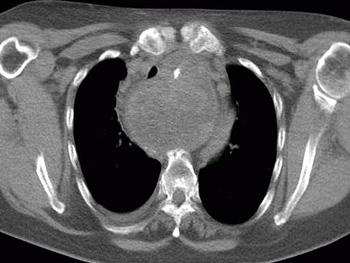

Bei besonders grossen Strumen, vor allem bei Ausbreitung in den Brustkorb, hinter die Luftröhre oder die Speiseröhre ist für die Operationsplanung des Chirurgen eine sogenannte Schnittbilduntersuchung wichtig. Computertomographie (ohne Kontrastmittel !!) können wichtige Zusatzuntersuchungen vor einer Operation sein.

![]() |

Magnetresonanztomographie |

ein SPECT-CT |